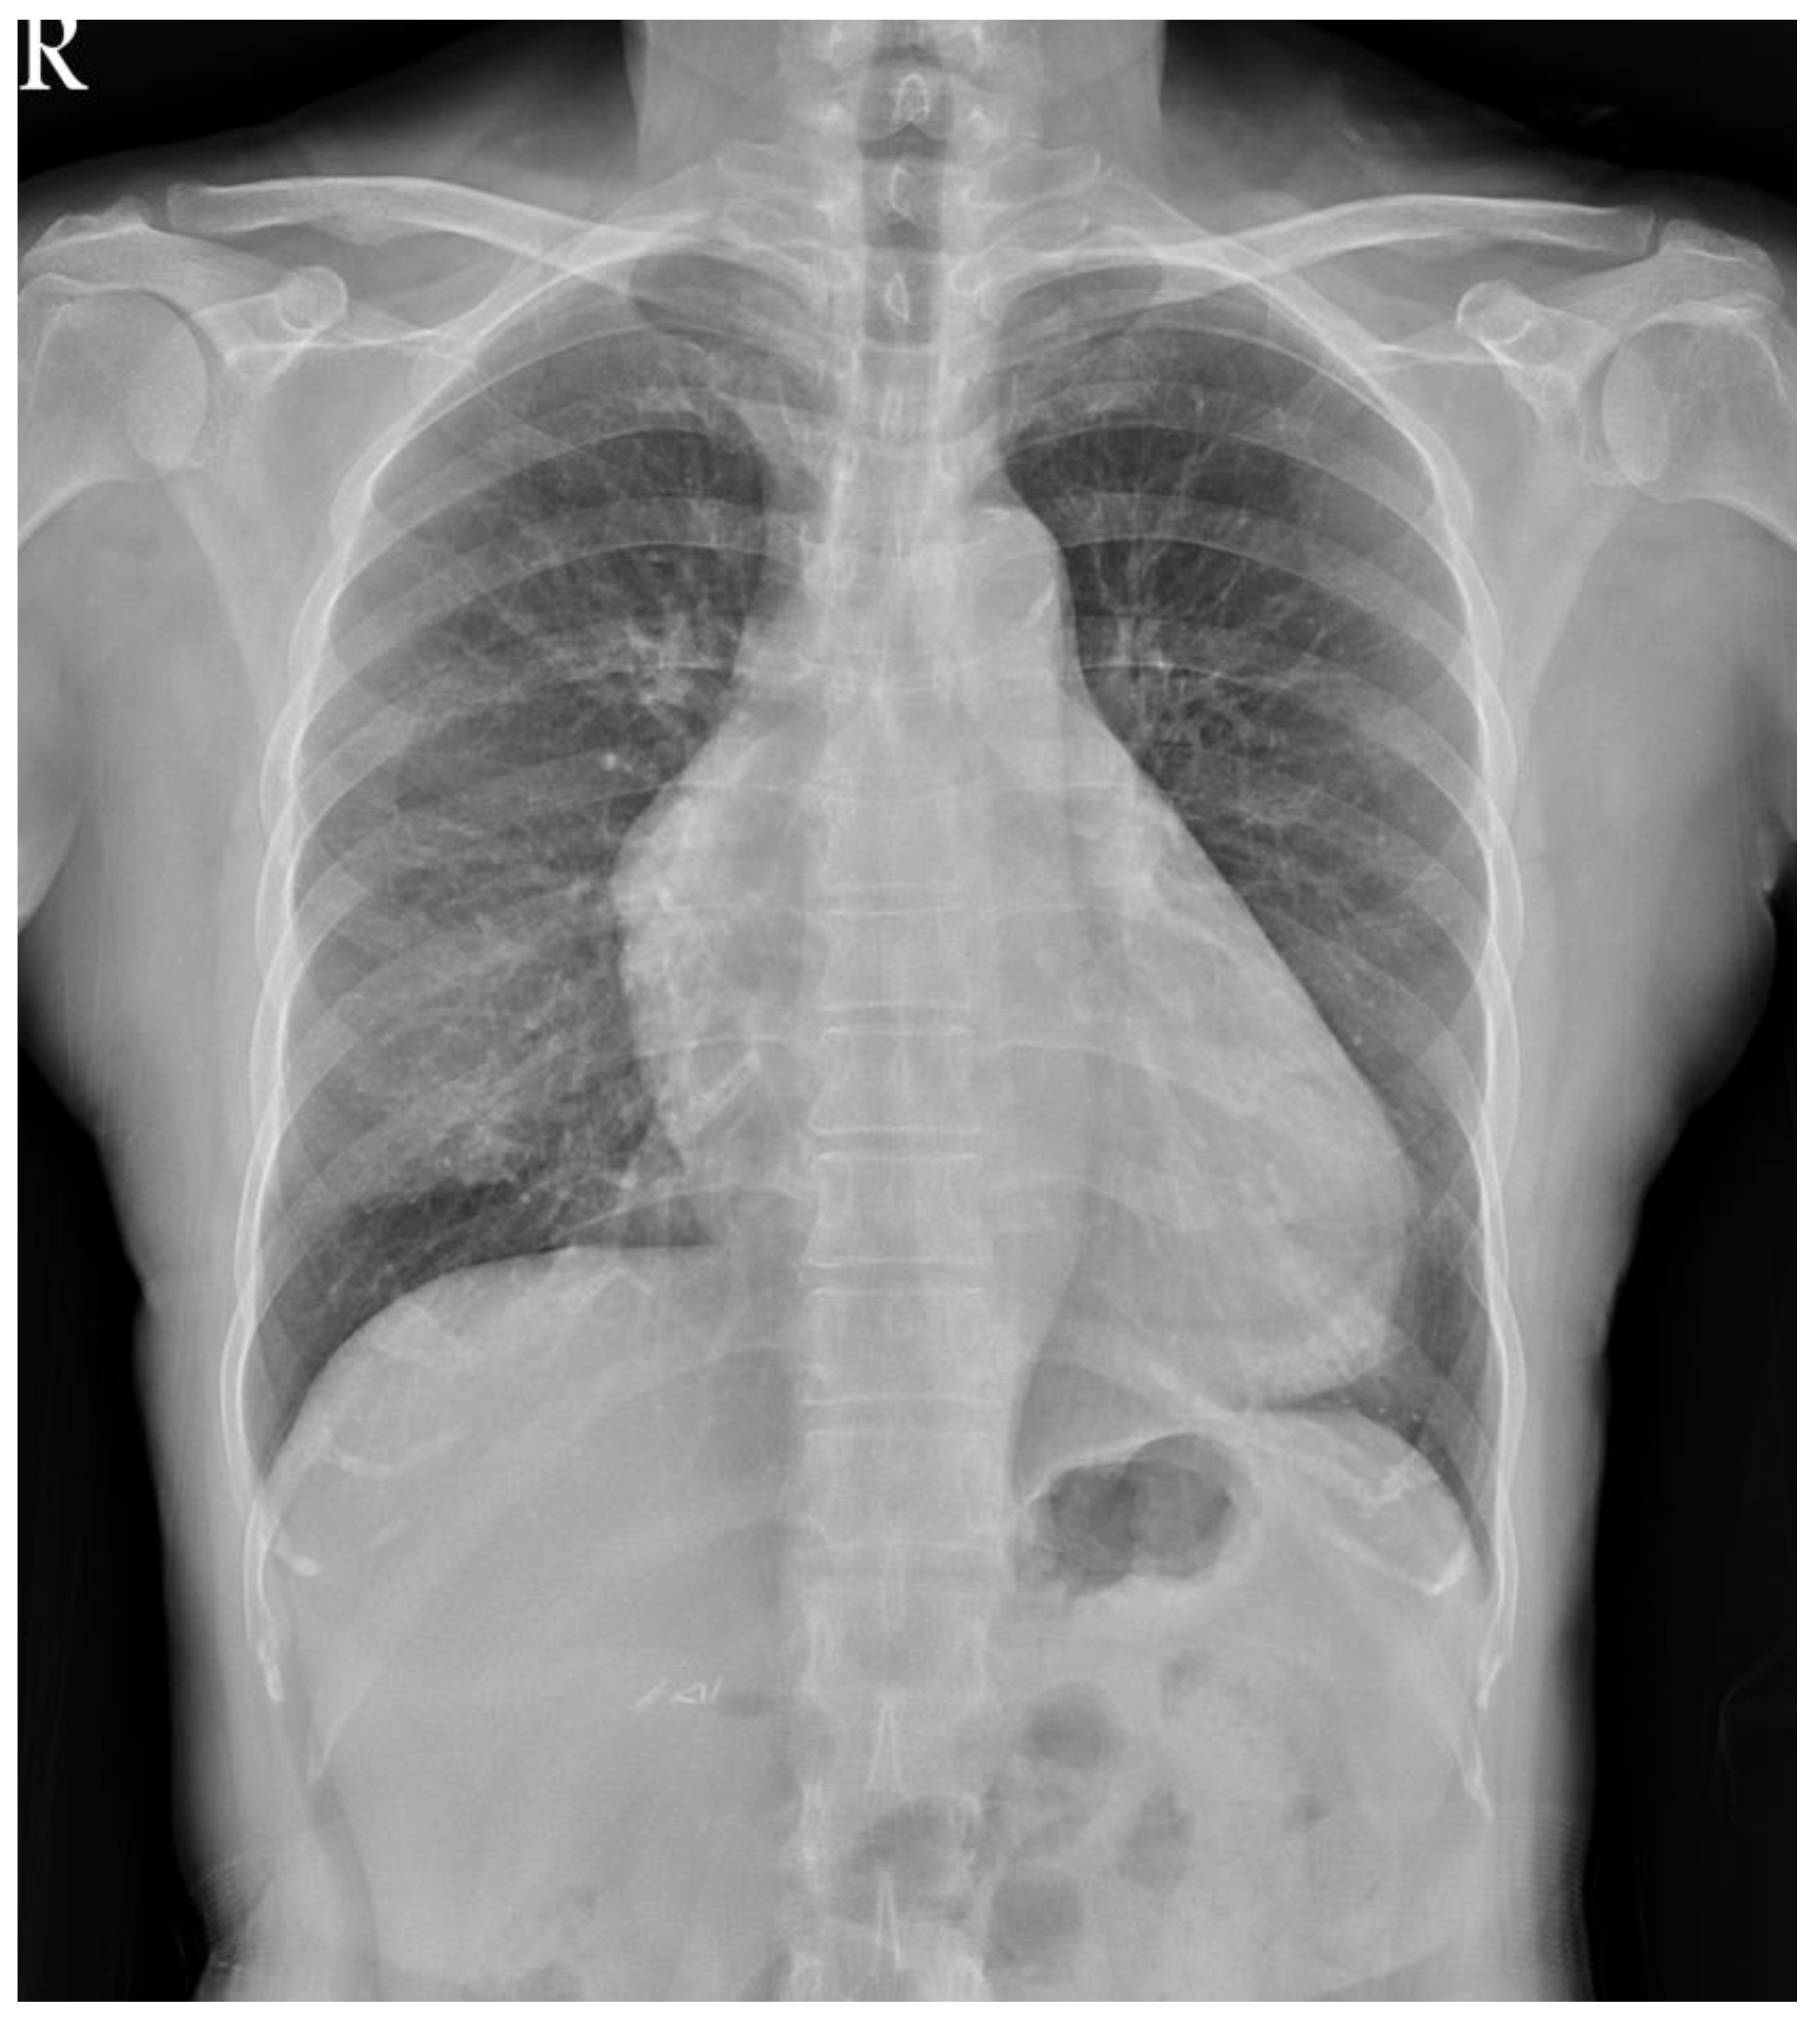

2. Detailed Case Description